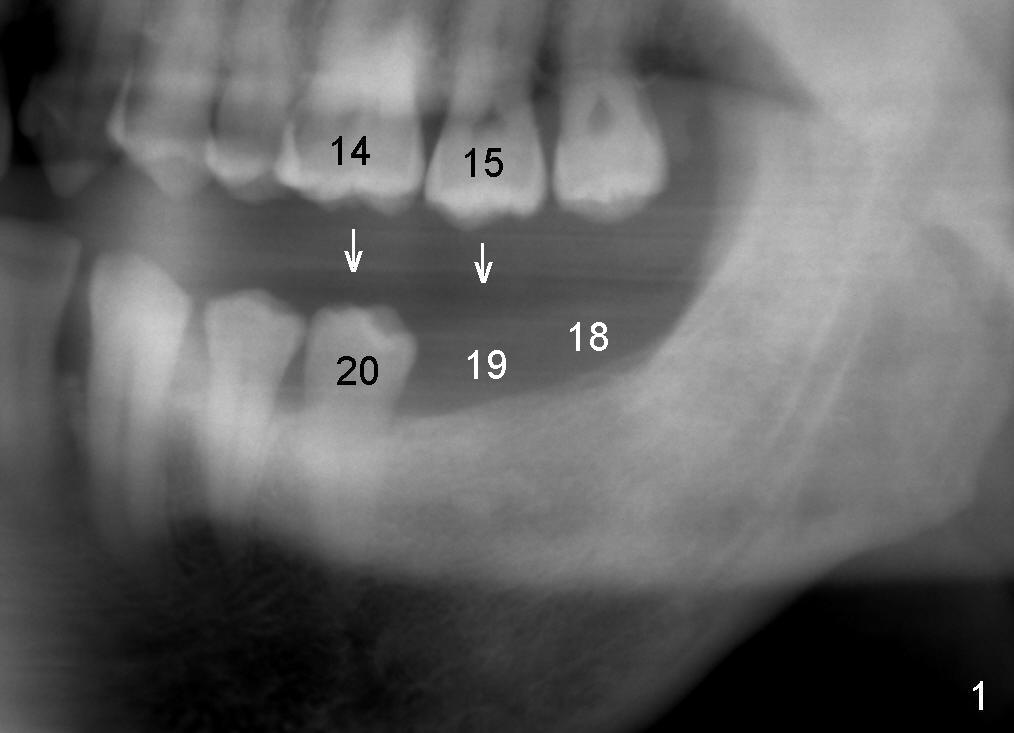

A 45-year-old man is a smoker (half pack a day). He returns for perio maintenance every 3 months. The teeth #18 and 19 have been extracted for long with supraeruption of #14 and 15 (Fig.1 arrows). CT confirms sufficient bone height (Fig.2) and width (Fig.3). Bone density is type II, as shown by CT and drilling. Relatively short implants are placed as deep as possible considering supraeruption of the opposing teeth (Fig.4 (4.5x14 and 5x14 mm taps at sites of #19 and 18, respectively) and Fig.5 (5x14 mm and 6x14 mm gingiva-level implants (I)). In order to avoid damaging the submandibular fossa, the implant at the site of #18 is tilted lingually (Fig.6). When short abutments (3 mm in height) are placed, there is enough clearance to place perio dressing. The abutment at the site of #18 becomes prematurely loose. It has to be removed 4 days postop. There is no sign of infection. Perio dressing is removed by the patient 7 days postop. He returns to clinic 8 days postop (Fig.7) for the remaining abutment to be removed. The wound appears to be healing normally.